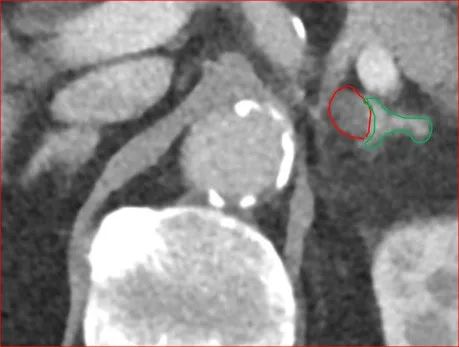

术前肾上腺增强CT检查:左侧肾上腺腺瘤。

图1. 红色箭头指向左侧肾上腺腺瘤。

图2. 红色圆圈指示左侧肾上腺腺瘤。

图3. 左侧肾上腺腺瘤(红圈)。